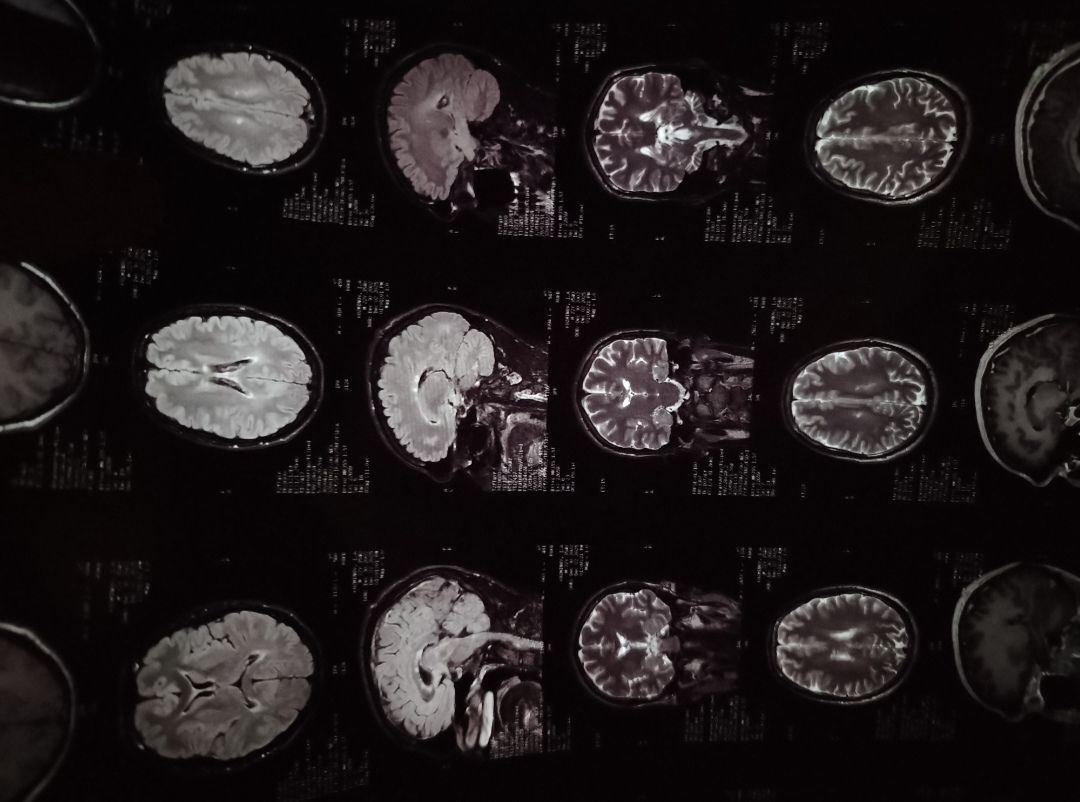

сделал мрт с контрастом, нашли рассеянный склероз (делал на 1,5 тесла, general electric, во время измерений слегка глотал слюну и самую малость приоткрывал глаза, что все вокруг было очень темным, с узким фовом)

из проблем

в прошлом году онемела половина тела, но тогда я выпил крепкий кофе, около 3х ложек. держалось неделю, распространено на правую часть тела

в этом году заметил покалывание в правой стопе, но думал изза привычки класть ногу куданибудь выше тела, стол, бортик кровати

сейчас размыло нахуй правый глаз, он видит только по окружности тестовых очков для определения диоптрий (?? был в частной клинике и они сами охуевали, там все с опытом и ранее лечил жкт, было очень быстро и комфортно, так что не отмажешься типа дауны сидели)

звон в ушах, иногда сильно накрывает. пиздец, пожил называется, хз что делать

22лвл